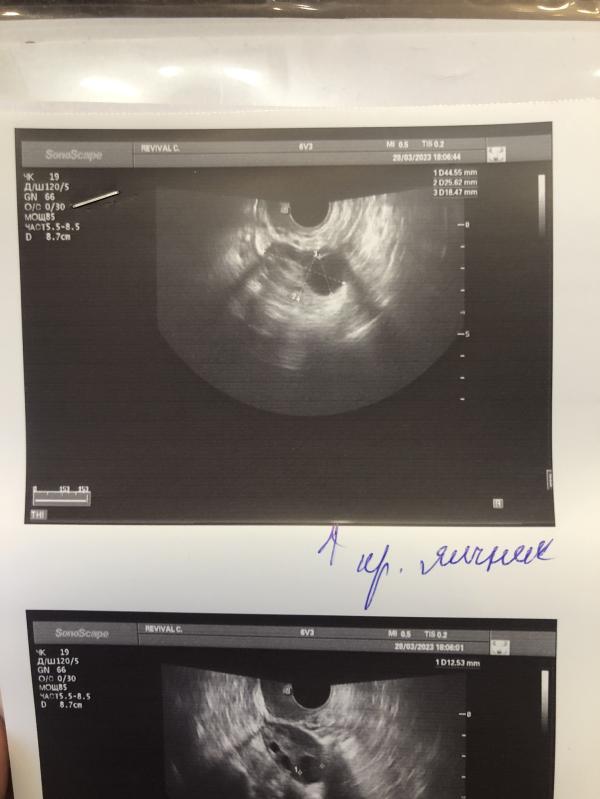

Я оправилась после первой неудачной стимуляции и решилась на вторую. Вчера был последний приём летрозола, сегодня 10 д.ц. и на фолликулометрии в правом яичнике показался хороший ДФ в 18 мм. Пожелайте мне, пожалуйста, удачи 🥰🥰🥰